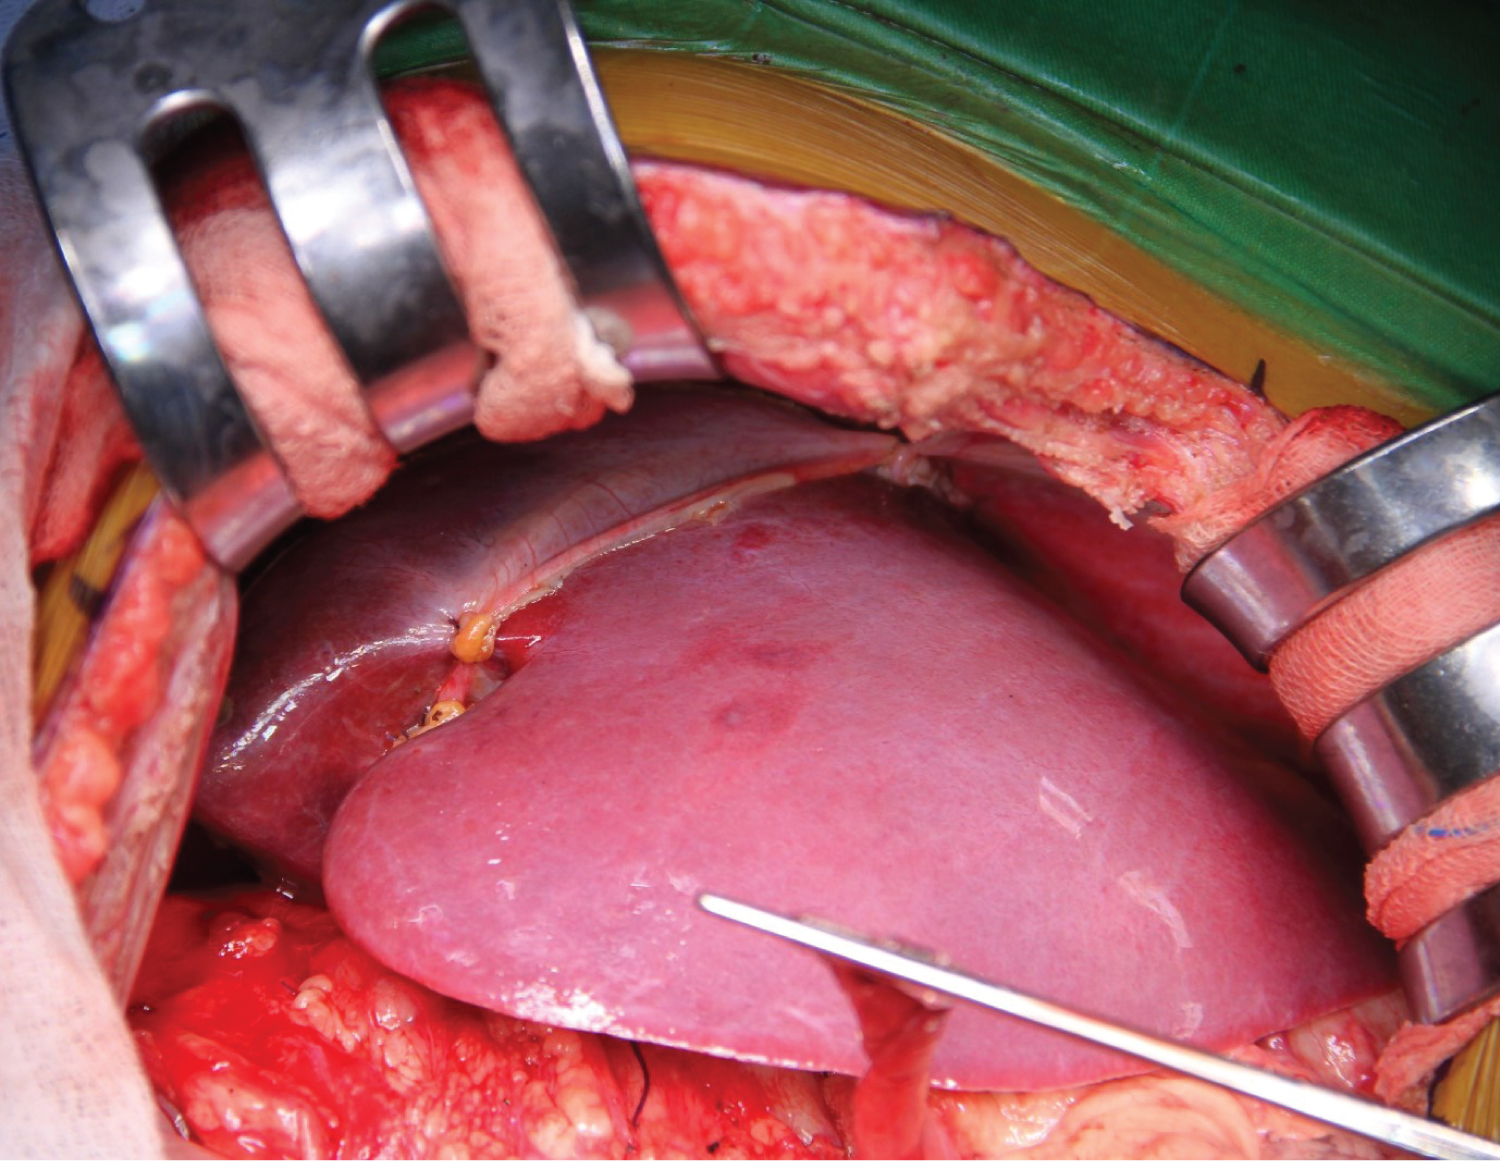

We aimed for mean arterial pressure (MAP) > 60 mmHg throughout the operation. 560g of liver tissue was removed from the patient (Figure 2). After the anastomoses of the great vessels were completed in the anhepatic phase of approximately 45 minutes, the clamp on the portal vein was removed, and reperfusion was achieved. The patient's blood pressure fell to 66/34 mmHg 2 minutes after reperfusion. The norepinephrine infusion dose was increased until his hemodynamics stabilized, and 5 mg of ephedrine and 100 mg of calcium chloride were given twice. In the intraoperative period, transesophageal echocardiography (TEE) provides invaluable information for closely monitoring pulmonary vascular resistance (PVR) and right ventricular functions in these patients. Since our patient had esophageal varices, we did not perform direct TEE, but when an extraordinary event occurred, we kept her at the patient's bedside to do it quickly. Our patient did not have pulmonary hypertension in the preoperative examination, and we tried to minimize the triggering factors that would increase PVR throughout the operation. We did not detect any increase in PVR in the measurement we made with PiCCO during the neo-hepatic phase. In the neo-hepatic phase, the dose of norepinephrine was reduced as the patient's hemodynamics returned to normal. Fluid therapy was performed considering the PiCCO parameters. The estimated blood loss during surgery was less than 250 mL. During the surgery, the patient was given a total of 1300 mL crystalloid, 1300 mL 5% albumin-containing colloid and 200 mL cell-caver, and 450 mL urine output was achieved. The inserted liver weighed 285g (Figure 3), and the operation continued for 7 hours. After the operation, she was taken to the intubated ICU and connected to a mechanical ventilator. While the patient was being followed on the ventilator, her SaO 2 was between 0.46 and 86-92%. On the 2 nd postoperative day, SaO 2 remained at 90-95%, hypoxemia resolved, weaning was applied, and the patient was weaned from the ventilator. After 2 days of oxygen support with a 2 L/min mask, she breathed in normal room air. After extubation, the patient's general condition and neurological examination were normal. Blood gas values, lactate level and hepatic transaminases returned to normal within days. Immunosuppressive drugs, steroids and nutritional support were administered to the patient. The patient was transferred to the service on the 4 th day after her follow-up in the ICU, and her follow-up continued. The patient was discharged 15 days after the operation without complications in the postoperative period.

Figure 2: 560g of liver tissue was removed from the patient.

Figure 3: The inserted liver weighed 285g.